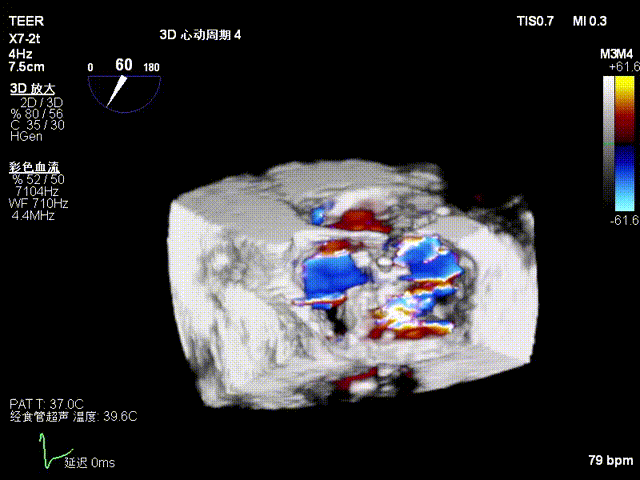

经食道超声检查提示:二尖瓣瓣叶增厚冗长2区后瓣脱垂呈连枷样改变,考虑Barlow’s综合征。评估解剖结构:前叶长度:3.3cm,后叶长度:2.8cm,脱垂宽度:26mm,脱垂高度:19mm,瓣口面积:7.5cm²。

术前影像

3D

X-plane 2区彩色